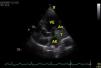

Em virtude de queixas de dispneia e dor retroesternal recorrente, sem alterações eletrocardiográficas de novo e sem elevação dos biomarcadores de necrose miocárdica, o doente fez TAC torácica, que mostrou uma massa hipodensa aparentemente extracardíaca, em relação com a aurícula esquerda. Um segundo ecocardiograma foi então realizado, tendo-se observado uma massa adjacente à aurícula esquerda (39×40mm), cuja continuidade com as cavidades cardíacas era duvidosa (Figuras 1 e 2). Foi então efetuada uma Ressonância Magnética Cardíaca que demonstrou a presença de um volumoso aneurisma ínfero-basal do ventrículo esquerdo, parcialmente preenchido por trombo de grandes dimensões (52×48×32mm). Dada a reduzida espessura da parede deste aneurisma, não foi possível distinguir nela as várias camadas da parede, pelo que não se pôde excluir em definitivo um pseudo-aneurisma com apresentação tardia. Existia algum fluxo entre o trombo e o fundo-de-saco do aneurisma que, no entanto, parecia aderente às paredes do aneurisma nas extremidades superior e inferior (Figuras 3 e 4). Este exame confirmou o compromisso severo da função ventricular esquerda e a insuficiência mitral, por alteração da geometria do ventrículo esquerdo, com marcado repuxamento do folheto posterior.

DiscussãoO diagnóstico entre aneurisma ventricular esquerdo e pseudo-aneurisma é difícil, especialmente quando o aneurisma tem uma localização posterior (3%)2,3. Os verdadeiros aneurismas são definidos como áreas de miocárdio mais fino, discinético, mas constituído por todas as camadas da parede. Por outro lado os pseudo-aneurismas resultam da rotura da parede livre, contida muitas vezes por trombo e pericárdio aderente. Os pseudo-aneurismas do ventrículo esquerdo apresentam assim maior risco de complicações, quando comparados com os aneurismas verdadeiros, sendo a mais grave a rotura espontânea, que resulta geralmente em morte súbita. O diagnóstico diferencial das duas situações é difícil, sendo muitas vezes um diagnóstico cirúrgico, pois têm muitas características comuns4. Um miocárdio fino ou com rotura move-se discineticamente ou não contrai, conduz à ocorrência de insuficiência cardíaca e arritmias ventriculares malignas, podendo estas ocorrer em ambas as patologias5. A deteção da massa adjacente à aurícula esquerda pela TAC e ecocardiografia tornou-se um desafio diagnóstico. A Ressonância Magnética Nuclear confirmou a existência de trombo associado a aneurisma/pseudo-aneurisma. No entanto, a dificuldade de detetar a continuidade do miocárdio, manteve-se com esta técnica. A intervenção cirúrgica, nos casos de aneurisma verdadeiro, visa melhorar a função do ventrículo esquerdo e reverter o remodelling, reduzindo a probabilidade de arritmias malignas, eventos embólicos e assim melhorar a sobrevida dos doentes com esta complicação.